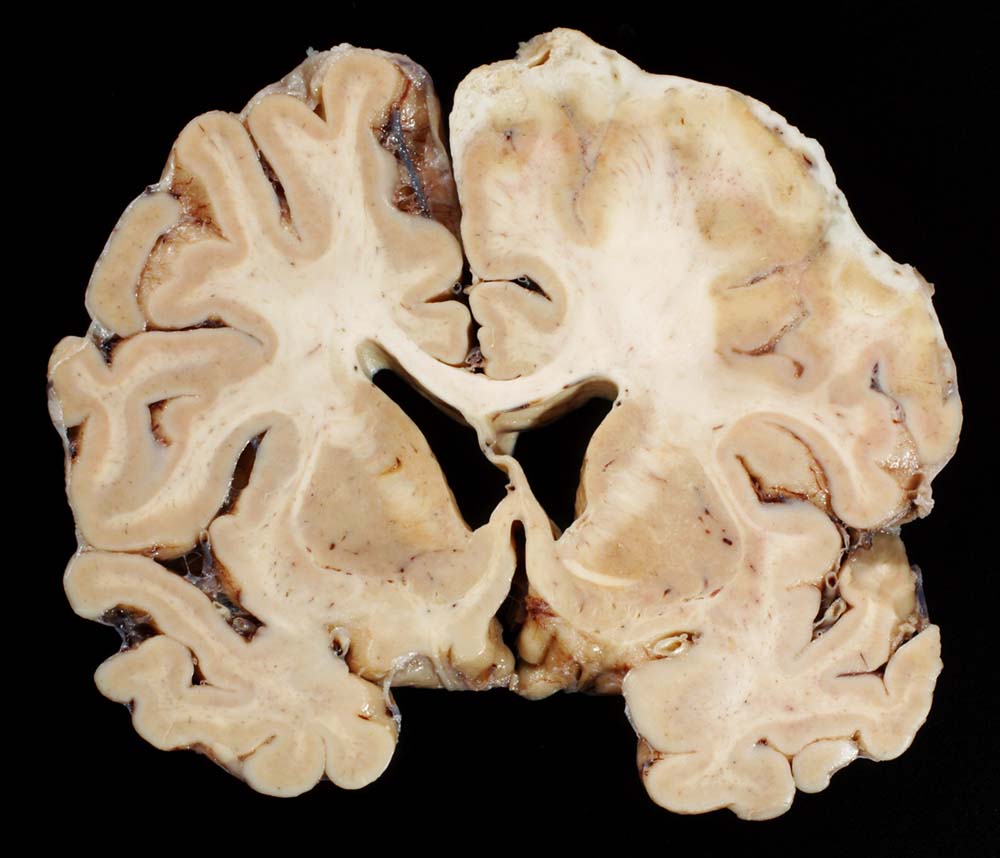

Eitrige Meningoenzephalitis (Pneumokokken), subdurales Empyem

Die rechte Hemisphäre ist überzogen von einer Eiterschicht und der angrenzende Cortex ist nekrotisch.

Chronischer Alkoholabusus. Diabetes mellitus. Hospitalisation in somnolentem febrilem Zustand im Rahmen einer Pneumokokkensepsis. Klinisch Ausschluss einer Endokarditis. Ischämie rechts frontotemporal mit schlaffer Hemiparese links. Unklarer neurologischer Zustand vermutlich metabolisch-toxischer Genese. Rhabdomyolyse bei St.n. Liegetrauma. Niereninsuffizienz. Tracheotomie wegen respiratorischer Verschlechterung.